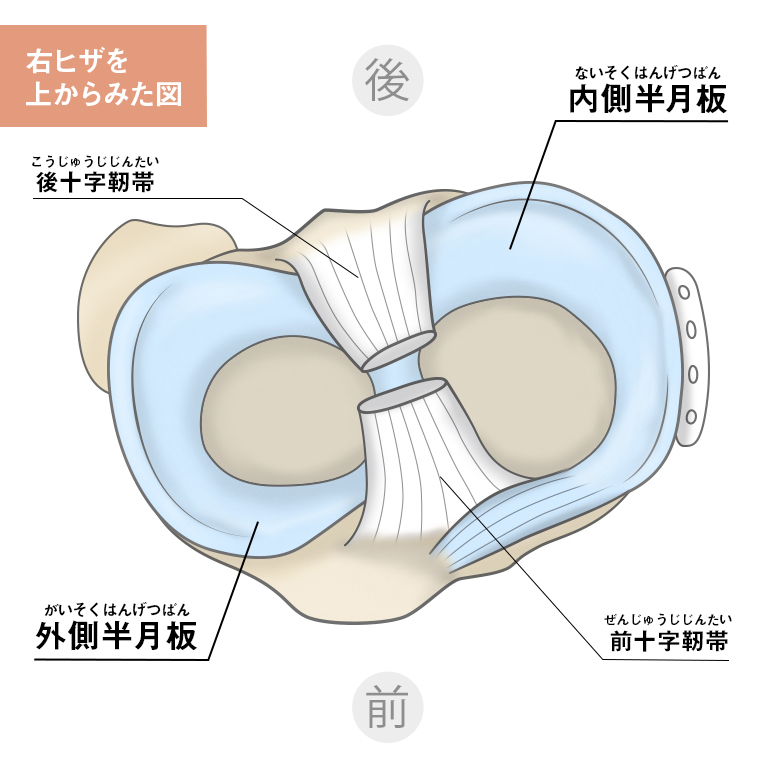

楽天市場】【内側半月板】《固定用》膝サポーター|エクスエイド。楽天市場】【内側半月板】《固定用》膝サポーター|エクスエイド。膝サポーター 膝 サポーター 医療用 医療 スポーツ 内側半月板。米10キロ 天のつぶ 雪若丸(各5キロ×1袋)。内側半月板損傷|おすすめの膝サポーター。半月板損傷 |SPORTS MEDICINE LIBRARY|ザムスト(ZAMST)。内側半月板損傷におすすめの膝サポーター集 コルセットミュージアム。半月板損傷 |SPORTS MEDICINE LIBRARY|ザムスト(ZAMST)。半月板損傷(断裂)meniscus-injury(rupture)について | ゆうき。右膝内側半月板損傷 前野整形外科 - 【公式】esaote 日本で唯一。外側半月板損傷|おすすめの膝サポーター。エクスエイドニー 固定用内側半月板損傷用 右膝用です。半月板損傷 – McDavid|サポータ-ブランドのマクダビッド。※外側半月板損傷 左膝膝としても使えます定価16980円でした。1度着用いたしました。円板状半月板損傷を治す!>膝サポーターのメソッド。固定力がとてもあり、安定してます。サイズM